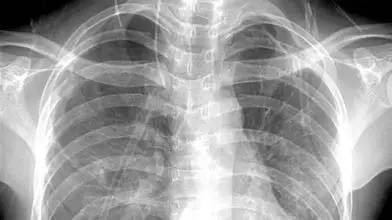

胸部——粗看X线片,细看CT,看肺不要选核磁

X线胸片可粗略检查心脏、主动脉、肺、胸膜、肋骨等,可以检查有无肺纹理增多、肺部钙化点、主动脉结钙化等。

胸部CT检查显示出的结构更清晰,对胸部病变检出敏感性和显示病变的准确性均优于常规X线胸片,特别是对于早期肺癌确诊有决定性意义。但是CT检查的辐射剂量高于X线。核磁对于肺部疾病的诊断,应用非常有限。